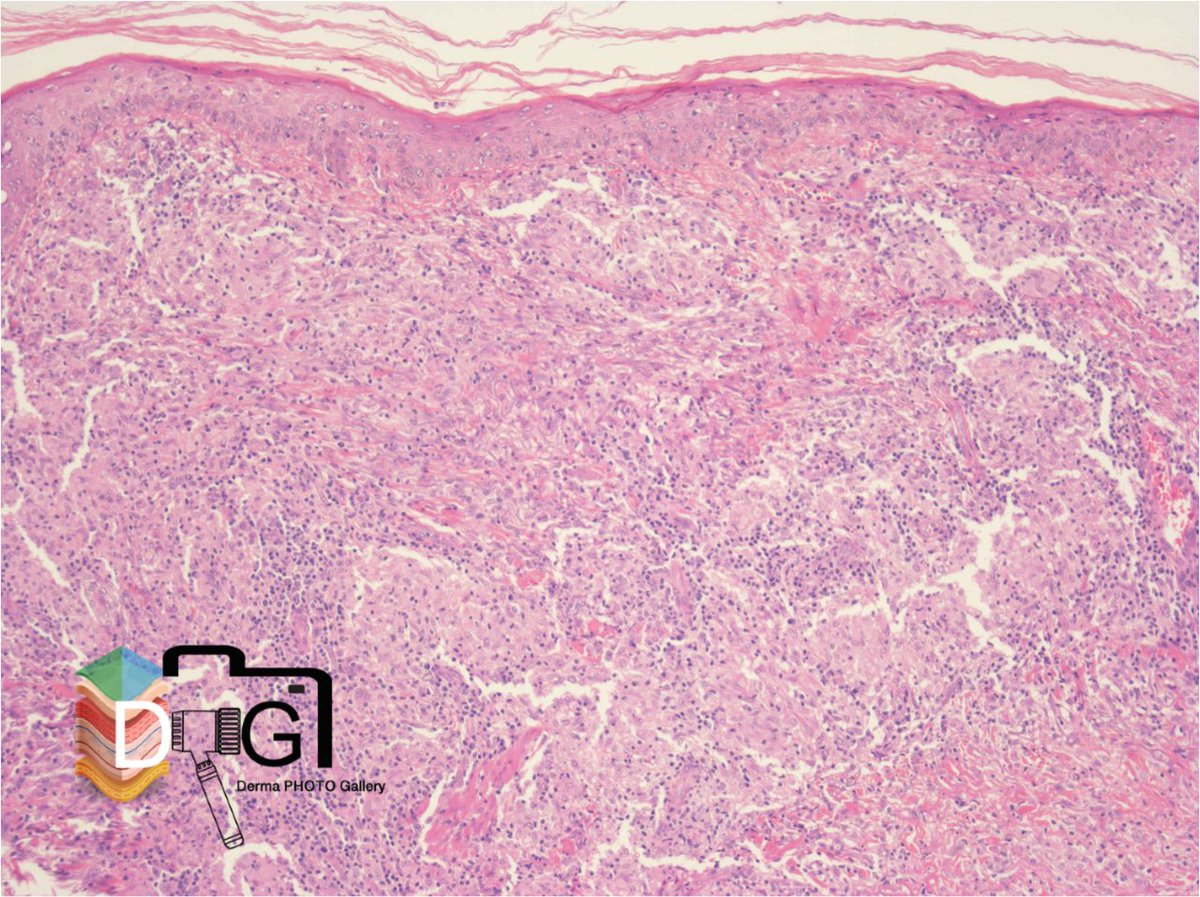

HISTOPATOLOGIA E INMUNOLOGIA DE LA LEPRA VII. 1/4

LEPRA TUBERCULOIDE SUBPOLAR (TTs). 1/2

Granulomas con signos activación epitelioide y menor circunscripción

Células gigantes tipo Langhans

Linfocitos con distribución + difusa respecto a macrófagos

Borramiento de la banda de Unna ImageImage

HISTOPATOLOGIA E INMUNOLOGIA DE LA LEPRA VII. 2/4

LEPRA TUBERCULOIDE SUBPOLAR (TTs). 2/2

Infiltrados liquenoides. Posible erosión epidérmica

Lesión neural importante

Los macrófagos de la lepra tuberculoide no expresan S-100

Marcada hiperplasia de células de Langerhans ImageImage